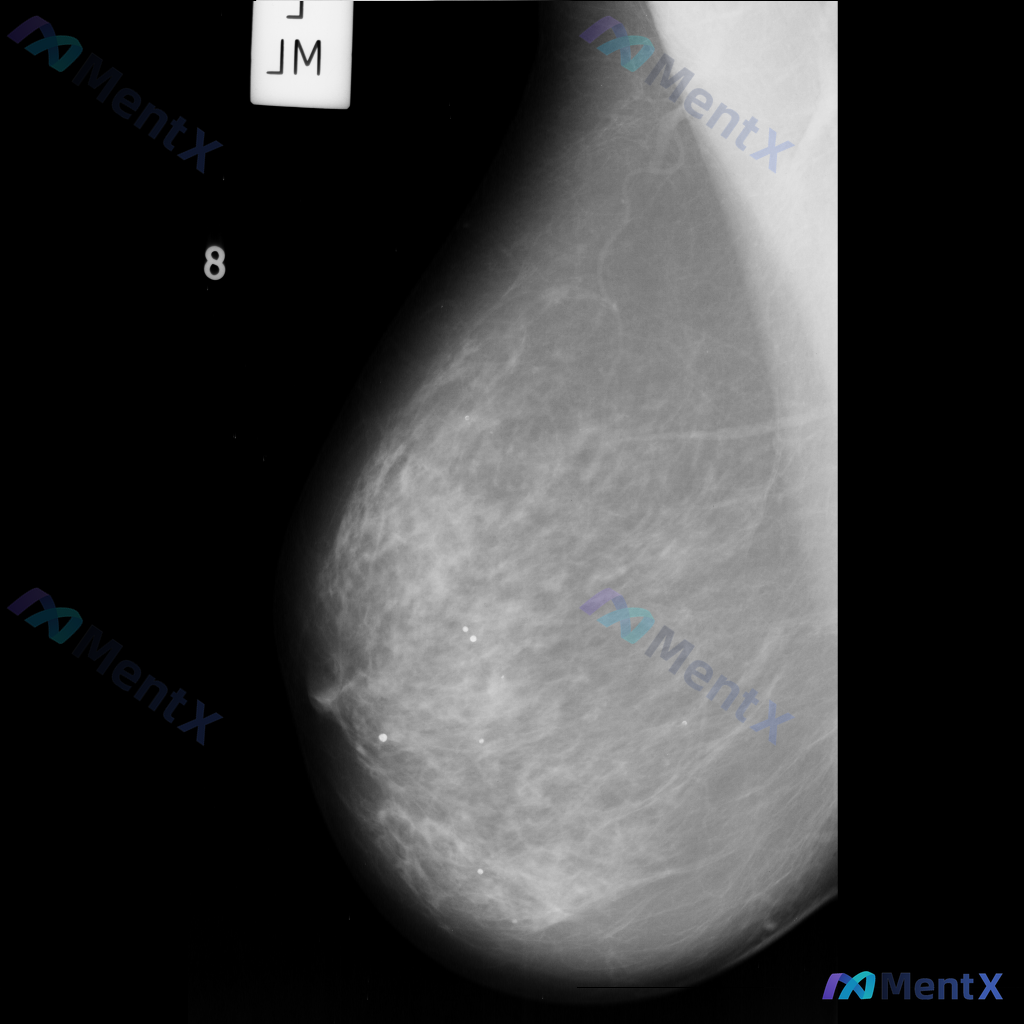

整理到一张单侧乳腺钼靶影像的读片资料,目前是单一体位图像,没有双侧对比。 影像表现整理 - 乳腺组织密度较高,属于多量腺体型或致密型背景 - 可见散在的钙化灶:图像中部偏下有数个点状或粗大钙化,形态不规则,但无典型恶性钙化的细小多形性、线样或分支状表现 - 乳腺下象限可见多个高密度圆形/卵圆形影,边...

整理到一组乳腺钼靶影像的资料,分享给大家讨论: - 背景:不均匀致密型乳腺(BI-RADS C类) - 主要异常: 1. 乳腺下象限靠近乳头乳晕区,见两个大小不一的圆形/卵圆形高密度影,还有一个较小的类圆形高密度影,密度高于周围腺体,边缘相对清晰但略显模糊; 2. 上述高密度影周围的乳腺下象限,腺体...